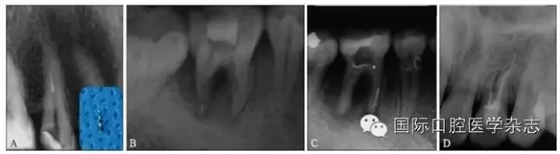

3.2.1 牙本質(zhì)厚度評(píng)估 取出分離器械需要損失部分牙本質(zhì),牙本質(zhì)的損失量包括縱向損失和橫向損失。縱向損失決定于取出時(shí)分離器械冠方末端需要暴露的長(zhǎng)度,橫向損失決定于分離器械的斷端直徑以及選用取出器械的方法(如超聲法或是環(huán)鉆法等)。牙本質(zhì)損失量過(guò)多會(huì)導(dǎo)致根管穿孔、根管折斷等并發(fā)癥[7](圖3)。

A:紅色及綠色的部分分別表示用改良GG鉆及超聲工作尖去除牙本質(zhì)的量;B:MicroCT掃描圖像顯示取出下頜第一磨牙近頰根管中分離器械后,導(dǎo)致了根管穿孔。

圖 3 取分離器械過(guò)程中會(huì)導(dǎo)致牙本質(zhì)損失,甚至穿孔等并發(fā)癥

取出分離器械后,根管壁的殘余牙本質(zhì)厚度是影響牙根抵抗力的重要因素,因而,可以認(rèn)為殘余牙本質(zhì)的厚度是影響分離器械取出與否的最重要的因素之一[8]。

根據(jù)Lim等[9]的研究顯示:為防止充填時(shí)產(chǎn)生折裂或穿孔等并發(fā)癥的發(fā)生,根管預(yù)備過(guò)后保存有200~300 μm的牙本質(zhì)厚度是必要的。如果牙本質(zhì)厚度低于一定值,這種情況下取出分離器械是有很大風(fēng)險(xiǎn)的,此時(shí),就不應(yīng)該貿(mào)然嘗試取出,而應(yīng)當(dāng)嘗試建立旁路通過(guò)分離器械或預(yù)備并充填至分離器械斷端平面;因此,操作之前應(yīng)當(dāng)進(jìn)行效益與風(fēng)險(xiǎn)的評(píng)估。